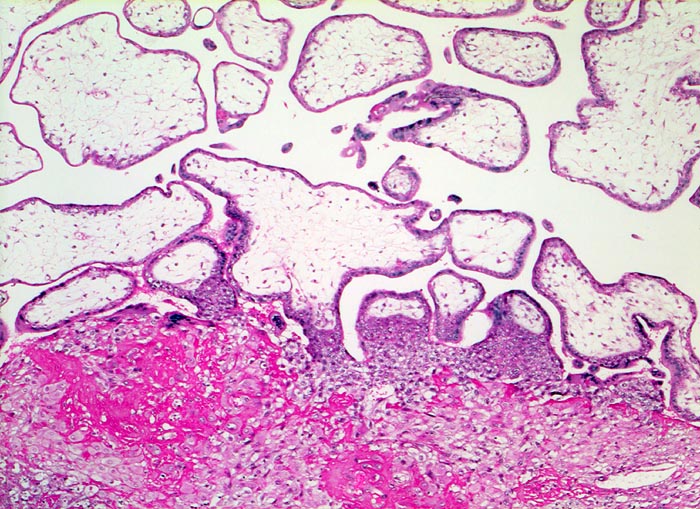

Morphologie:

• Plazenta accreta: Plazentarzotten haften dem Myometrium an ohne deziduale Zwischenschicht. Fibrin und Trophoblast kann vorhanden sein.

• Plazenta increta: Plazentaimplantation innerhalb des Myometriums.

• Plazenta percreta: Penetration der Plazentarzotten durch die gesamte Dicke des Myometriums hindurch.

Diagnosestellung im Ultraschall oder MRI. Früheste Diagnose in der 14. Schwangerschaftswoche berichtet. Ultraschallbild zeigt unregelmässige Aufhellungen des zottenhaltigen Plazentargewebes mit Ausbildung von ‚Lakunen’. Die Lakunen entstehen wahrscheinlich durch anomale Implantation und anomaler Position der Spiralarterien in Relation zum intervillösen Raum.